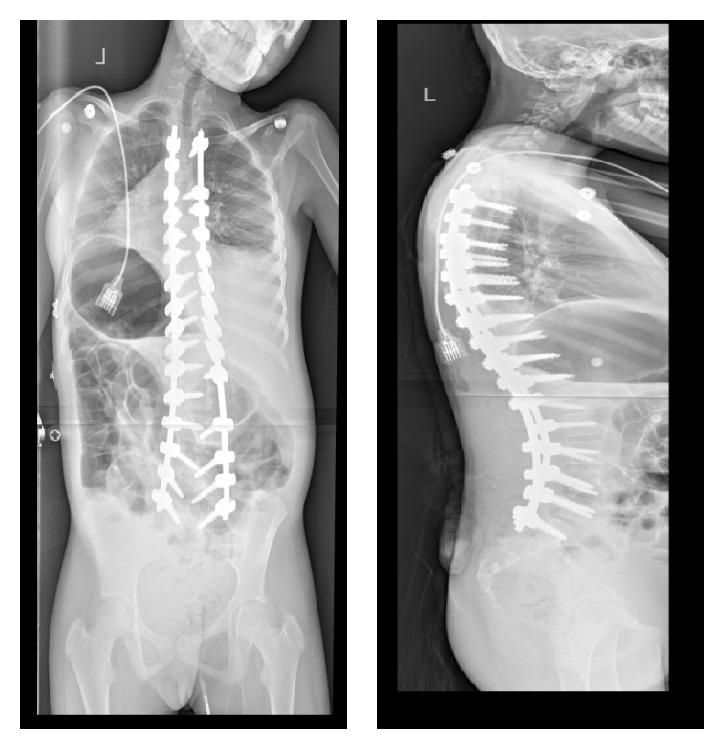

Minimally invasive surgery (MIS) has been described in the treatment of adolescent idiopathic scoliosis (AIS) and adult scoliosis. The advantages of this approach include less blood loss, shorter hospital stay, earlier mobilization, less tissue disruption, and relatively less pain. However, despite these significant benefits, MIS approach has not been reported in neuromuscular scoliosis patients. This is possibly due to concerns with longer surgery time, which is further increased due to more levels fused and instrumented, challenges of pelvic fixation, size and number of incisions, and prolonged anesthesia. We modified the MIS approach utilized in our AIS patients to be implemented in our neuromuscular patients. Our technique allows easy passage of contoured rods, placement of pedicle screws without image guidance, partial/complete facet resection, and all standard reduction maneuvers. Operative time needed to complete this surgery is comparable to the standard procedure and the majority of our patients have been extubated at the end of procedure, spending 1 day in the PICU and 5-6 days in the hospital. We feel that MIS is not only a feasible but also a superior option in patients with neuromuscular scoliosis. Long-term results are unavailable; however, short-term results have shown multiple benefits of this approach and fewer limitations.

微创手术(MIS)已被应用于青少年特发性脊柱侧凸(AIS)和成人脊柱侧凸的治疗。这种方法的优点包括失血少、住院时间短、早期活动、组织损伤小以及疼痛相对较轻。然而,尽管有这些显著益处,但尚未有关于神经肌肉型脊柱侧凸患者采用MIS方法的报道。这可能是由于担心手术时间较长,而由于融合和固定的节段更多、骨盆固定的挑战、切口的大小和数量以及麻醉时间延长,手术时间会进一步增加。我们对用于AIS患者的MIS方法进行了改良,以便应用于神经肌肉型患者。我们的技术允许塑形棒轻松通过、在无影像引导的情况下置入椎弓根螺钉、部分/完全关节突切除以及所有标准的复位操作。完成该手术所需的手术时间与标准手术相当,并且我们的大多数患者在手术结束时已拔管,在重症监护病房(PICU)待1天,住院5 - 6天。我们认为MIS对于神经肌肉型脊柱侧凸患者不仅是一种可行的选择,而且是一种更好的选择。长期结果尚不可得;然而,短期结果已显示出这种方法的多种益处且局限性较少。